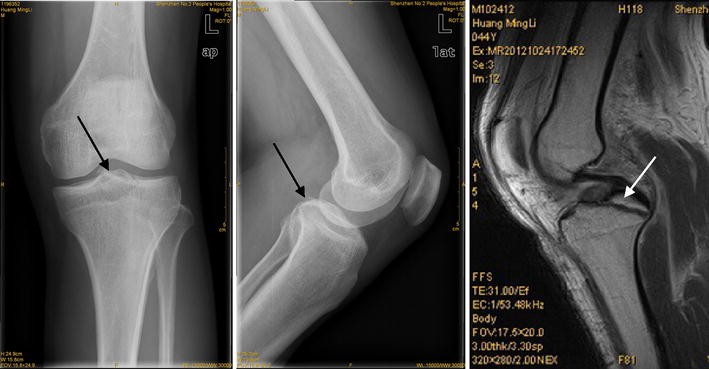

A partial acl tear occurs when only part of the ligament is torn. At the top of the tibia, there are the medial and lateral condyles, which are slightly convex surfaces that correspond to the condyles of the femur. How to tell if you have anterior cruciate ligament injury. The anterior cruciate ligament (acl) is located inside your knee joint and connects the bones of your upper and lower leg. Magnetic resonance (mr) imaging has emerged as the study of choice to evaluate the status of the acl and other associated structures in the knee. Anterior Cruciate Ligament Rupture and Torn Meniscus.

External loads associated with anterior cruciate ligament injuries increase the correlation between tibial slope and ligament strain during in vitro simulations of in vivo landings clin biomech (bristol, avon). Physical examination for the assessment of the acl is commonly used in routine care in the evaluation of the knee and is part of the diagnostic process. Anterior cruciate ligament (acl) injuries are typically the result of a noncontact pivoting injury (70%). Magnetic resonance (mr) imaging has emerged as the study of choice to evaluate the status of the acl and other associated structures in the knee. These injuries are relatively uncommon. PrettyCare Knee Brace Support ( Professional Protection.